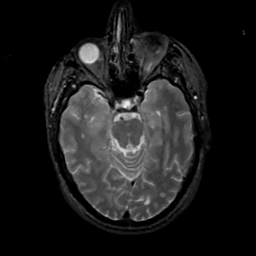

MR Study #14, June 2, 1991 -- Slice #18